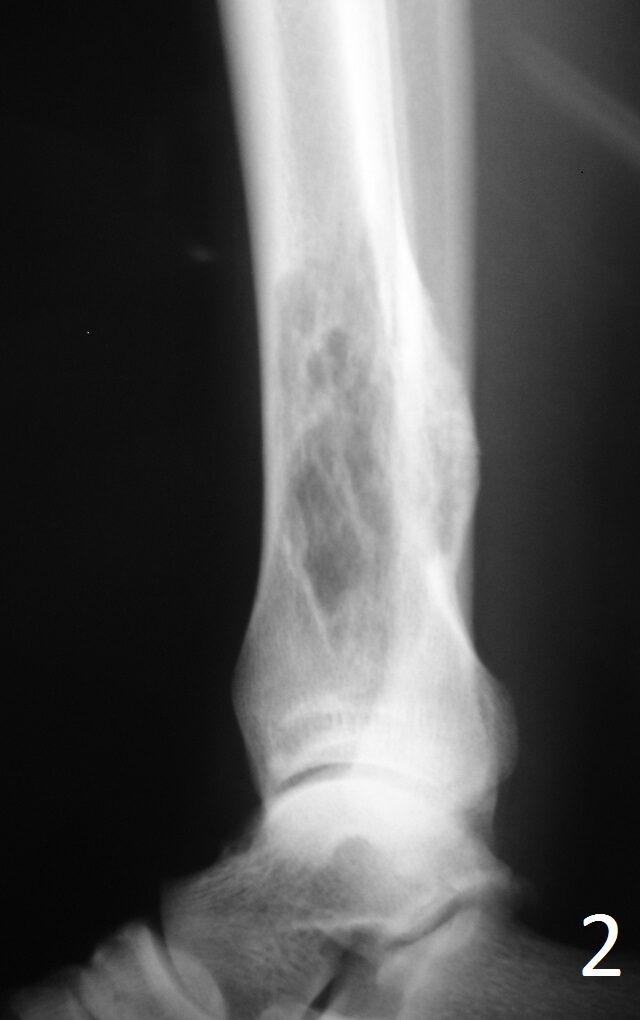

Plain x-ray (Fig. 1-2)

• Well-defined, lucent and expansile

• Possible cortical degradation

• Possible involvement of soft tissue

• More destructive, aggressive growth

• Shown by less-defined borders

• Pathologic fracture may occur

• Described as moth eaten